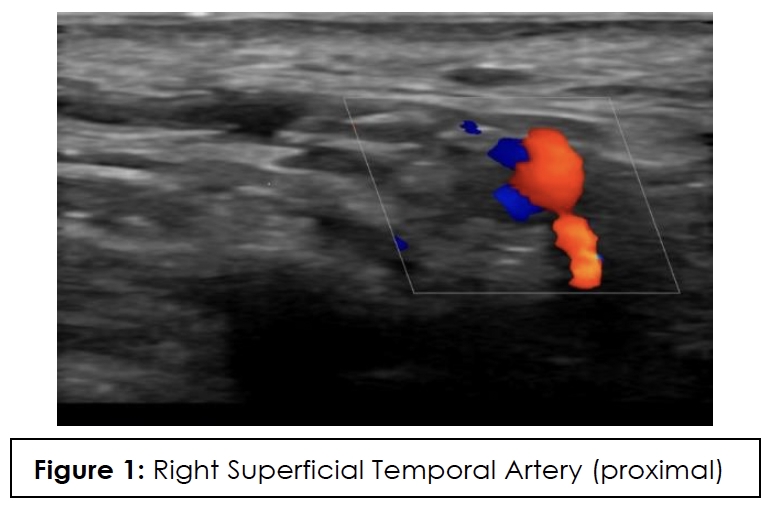

ESR, CRP, and color Doppler ultrasound (CDUS) of his temporal artery in July 2023 were negative, showing no GCA in the superficial temporal arteries. CDUS of bilateral temporal arteries demonstrated normal flow characteristics (Figures 1,2,3,4). Physical examination and temporal predominance of headache prompted obtaining the temporal artery biopsy in August 2023, which revealed healing GCA (Figure 5). The presence of myxoid change in the asymmetrically thickened intima and a residual infiltrate of mostly macrophages at the tunica intima-tunica media interface where the internal elastic lamina was absent allowed distinction of healing arteritis from age-related histopathological change, which may resemble healed giant cell arteritis. 3

In addition to laboratory results, color Doppler ultrasound (CDUS) of the temporal artery is now considered first-line for diagnosis because it has a higher sensitivity than temporal artery biopsy and is of lower cost and less invasive. The hallmark “halo sign,” visible on ultrasound, indicates inflammation of the vessel walls. Bilateral temporal “halo sign” is highly specific for GCA.36 In the 2016 TABUL study37 (a multi-center, prospective study for GCA), ultrasound had sensitivity of 54% and specificity of 81%, while temporal artery biopsy had sensitivity of 39% and specificity of 100%. Temporal artery biopsy remains the gold standard for diagnosis. The lower sensitivity of biopsy is likely due to skip lesions and prior corticosteroid treatment. Unexpectedly, our patient’s ultrasound was negative but biopsy was positive for GCA. Temporal artery abnormalities, including beading (irregular contour), prominence, tenderness, and an absent pulse, are reported to significantly increase the likelihood ratio for a positive temporal artery biopsy (TAB).38 Our patient had prominent temporal arteries on examination, giving him an increased likelihood of positive biopsy.

Ultrasound halo size abnormalities reduced after four or more days of high-dose glucocorticoid treatment. The percentage of positive biopsy results dropped significantly when patients began glucocorticoid treatment within 3 days.39 Our patient had the ultrasound performed approximately 20 days before starting the steroids, so the absence of the halo sign cannot be attributed to the steroids.